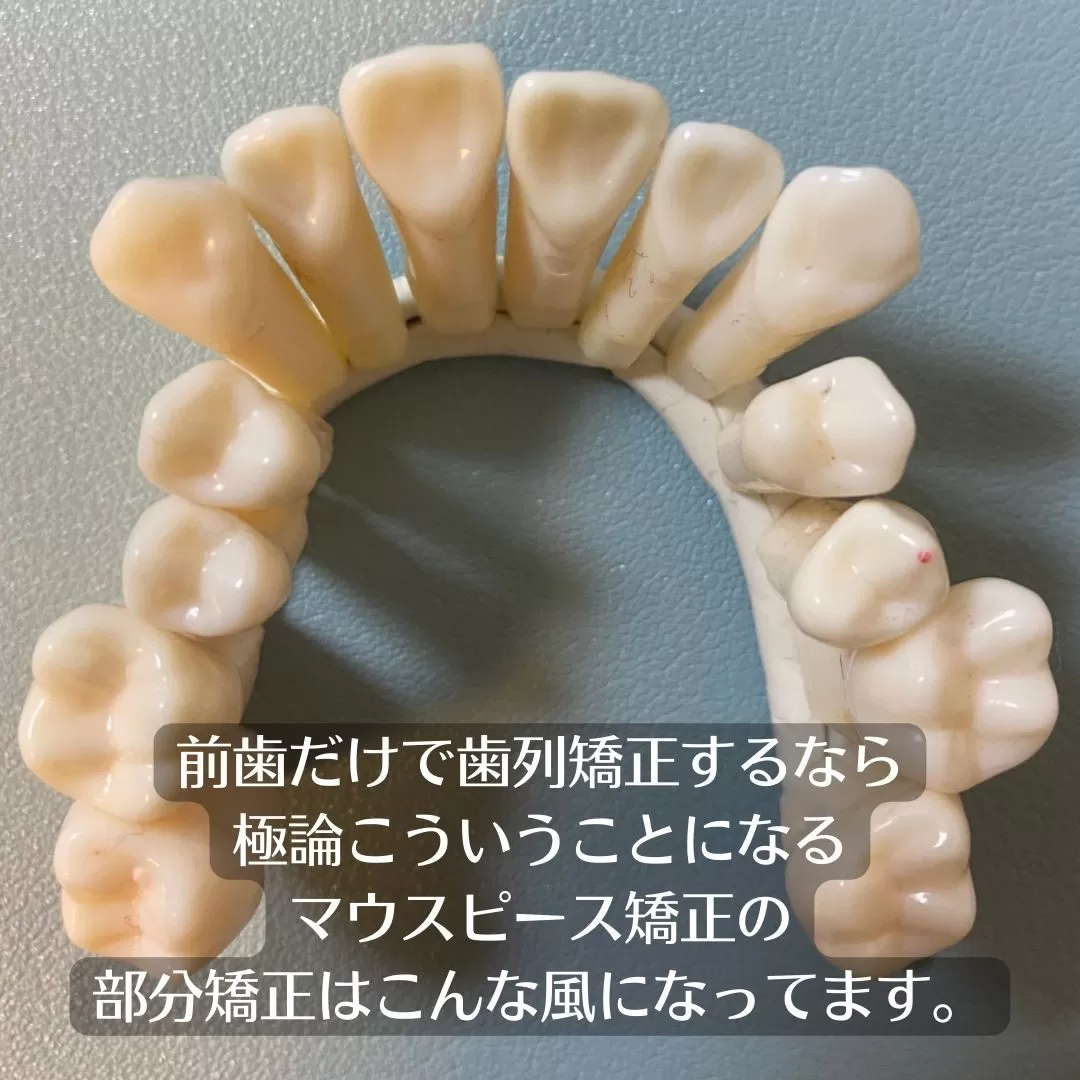

【極論をお話します。】

前歯だけが並びが悪く見えます。部分矯正で治すイメージですよね。

では模型を見てみましょう

極論ですが、こんな歯並びがあったとします。

前歯が気になるとして、前歯を部分矯正で考えるとこうなります。

そうなんです、部分で考えるとスペースを求めて

出るんです。